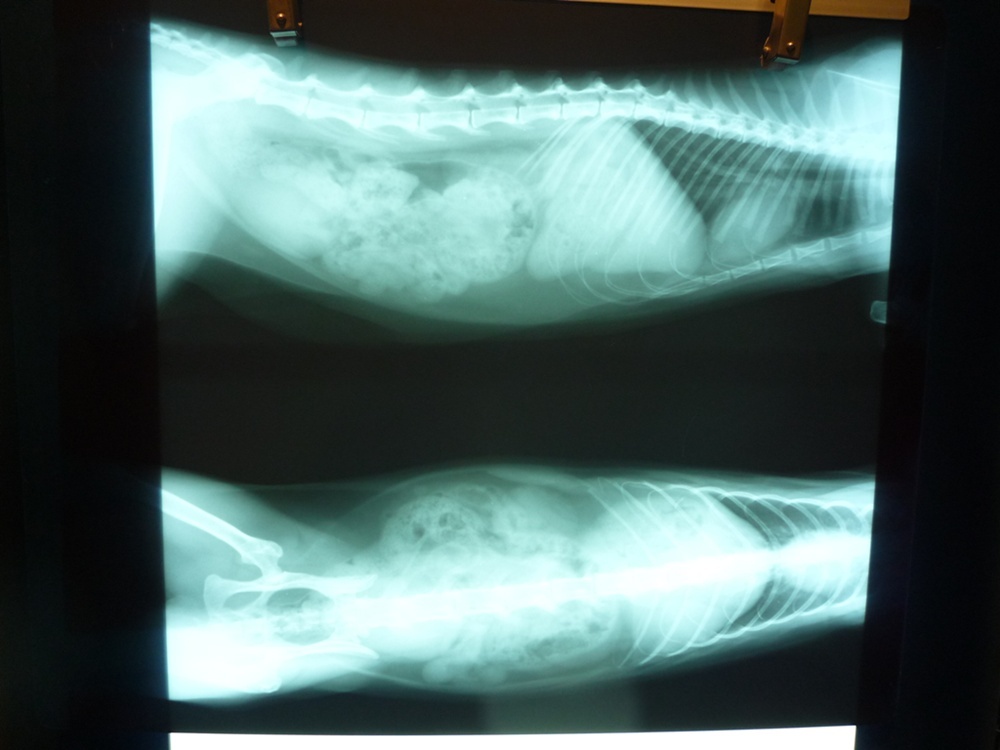

主題: 蹲在路邊尿尿有問題~ 申請者姓名: 陳曉霏 花色: 申請日期: 2012-10-26 01:51:03 申請者部落格: 申請者臉書網址: http://www.facebook.com/xiaofeic 所在縣市/合作醫院: 台北市/長沁動物醫院 治療費用: 5120元 需求人數: 7人 已結案 (2013-07-09 13:52:07) 報名人員: Lisa Cheng(已付款)、Lisa Cheng、Lisa Cheng、黃台芸、黃台芸、張雅筑(已付款)、Lulu Nova、陳小可(已付款)、周星星(已付款)、陳可可(已付款)、Ivy Chen(已付款)、Tiffany Shen(已付款)、 候補人員: 動物病情說明: 疑似走失的孩子

非常的親人

發現他時 正用著奇怪的姿勢蹲著想尿尿

但卻尿不出來!

餵他吃東西 他吃了就吐@@

醫生檢查後 發現他白血球偏高

還是一個愛滋的孩子~

尿濃度也很高

經過醫生細心的照顧下

目前狀況已經穩定